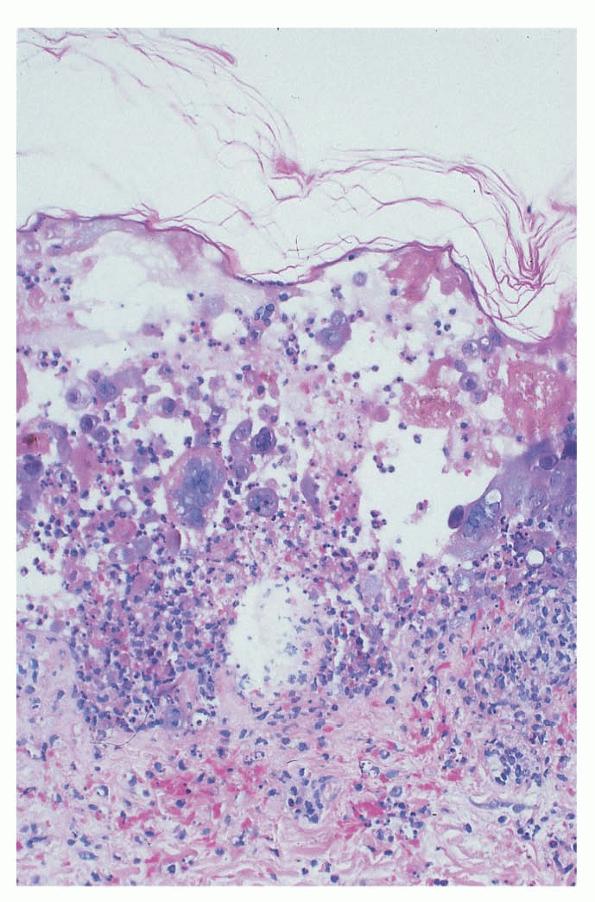

Herpes simplex = العقبول البسيط